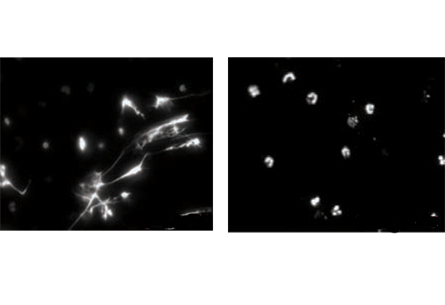

Neutrophils normally serve on the front lines against disease. But in one of the two new studies, Pascual and her colleagues show in lab tests that exposing neutrophils from lupus patients to abnormal antibodies, also from lupus patients, induces the neutrophils to die rapidly in culture. What’s pivotal is how the cells expire: The neutrophils’ components are extruded from the cell and form neutrophil extracellular traps, or NETs, weblike structures that comprise unwound strings of DNA, proteins and other cell components.

When neutrophils from healthy people were exposed to the rogue lupus antibodies, the cells didn’t release their contents in NETs.

Normally, sticky NETs can form in healthy people but serve an immune purpose by snagging bacteria or yeast, Pascual says. But when NETs are made in response to lupus antibodies, the resulting DNA-protein complex activates other immune cells (a kind of dendritic cell) and triggers overproduction of interferon alpha, a potent immune protein. Interferon alpha activates yet more cells in a cascade that the researchers hypothesize can lead to more abnormal antibody production and the inflammation that damages tissues in lupus patients.